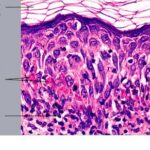

Histopathology. EM is considered the prototype of the vacuolar form of interface dermatitis . The early changes include vacuolization of the basal cell layer; tagging of lymphocytes along the dermal-epidermal junction; and a sparse, superficial, perivascular lymphoid infiltrate . Necrosis of individual keratinocytes in the basal unit occurs, which is the hallmark of EM. Because of its acute nature, there is an orthokeratotic stratum corneum. Mild spongiosis, papillary dermal edema, and extravasation of red blood cells are seen. As the lesion becomes more developed, there is a moderate lichenoid infiltrate of Iymphohistiocytes at the dermal-epidermal junction with exocytosis. More apoptotic keratinocytes within and above the basal epidermal layer are present. The |

intensity of epidermal necrosis varies from vacuolated individual keratinocytes surrounded by lymphocytes (satellite cell necrosis) at the basal unit to confluent necrosis in association with intraepidermal and subepidermal vesicles. The dermal infiltrate comprises lymphocytes and histiocytes. Eosinophils may also be present. Although one study has noted a significant number of eosinophils in drug-induced EM, this has not been noted by others. In the authors’ estimation, a generous number of eosinophils exclude EM. One study has found that an acrosyringium concentration of apoptotic keratinocytes in EM is a clue to a drug etiology . In early lesions of SJSITEN, apoptotic keratinocytes are observed scattered in the basal layer of the epidermis. In established lesions, there are numerous necrotic keratinocytes, even full-thickness epidermal necrosis, and a subepidermal bulla. The dermal inflammatory infiltrate is sparser in TEN than in EM (Fig. 9-278). Extravasated erythrocytes are commonly found within the blister cavity. Melanophages within the papillary dermis occur in late lesions. Eccrine epithelium shows a variety of changes from basal cell apoptosis to necrosis of the duct. |

In general, EM shows less epidermal necrosis, more dermal inflammation, and exocytosis, whereas SJS and TEN reveal more epidermal necrosis, less dermal inflammation, and exocytosis. However, due to the overlapping histologic features among EM, SJS, and TEN, histologic examination-while important for recognizing the spectrum of disorders-is not reliable for classifying the disease. Correlation with clinical presentation is essential. |